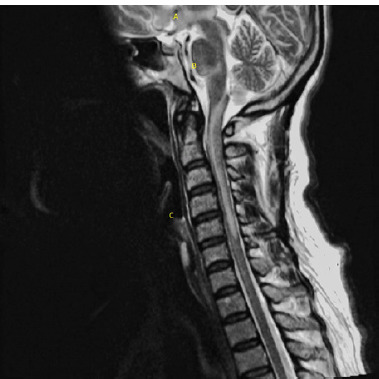

Case description: A 51-year-old woman presented with persistent holocranial headache, nausea, vertigo, and neurological deficits one month after a COVID-19 hospitalization. Neurological examination revealed hemiparesis, dysphagia, and ataxia. Imaging showed lesions in the central nervous system. A diagnosis of neurosarcoidosis was considered, supported by clinical criteria, imaging findings, and elevated ACE levels. Steroid therapy led to symptom improvement.